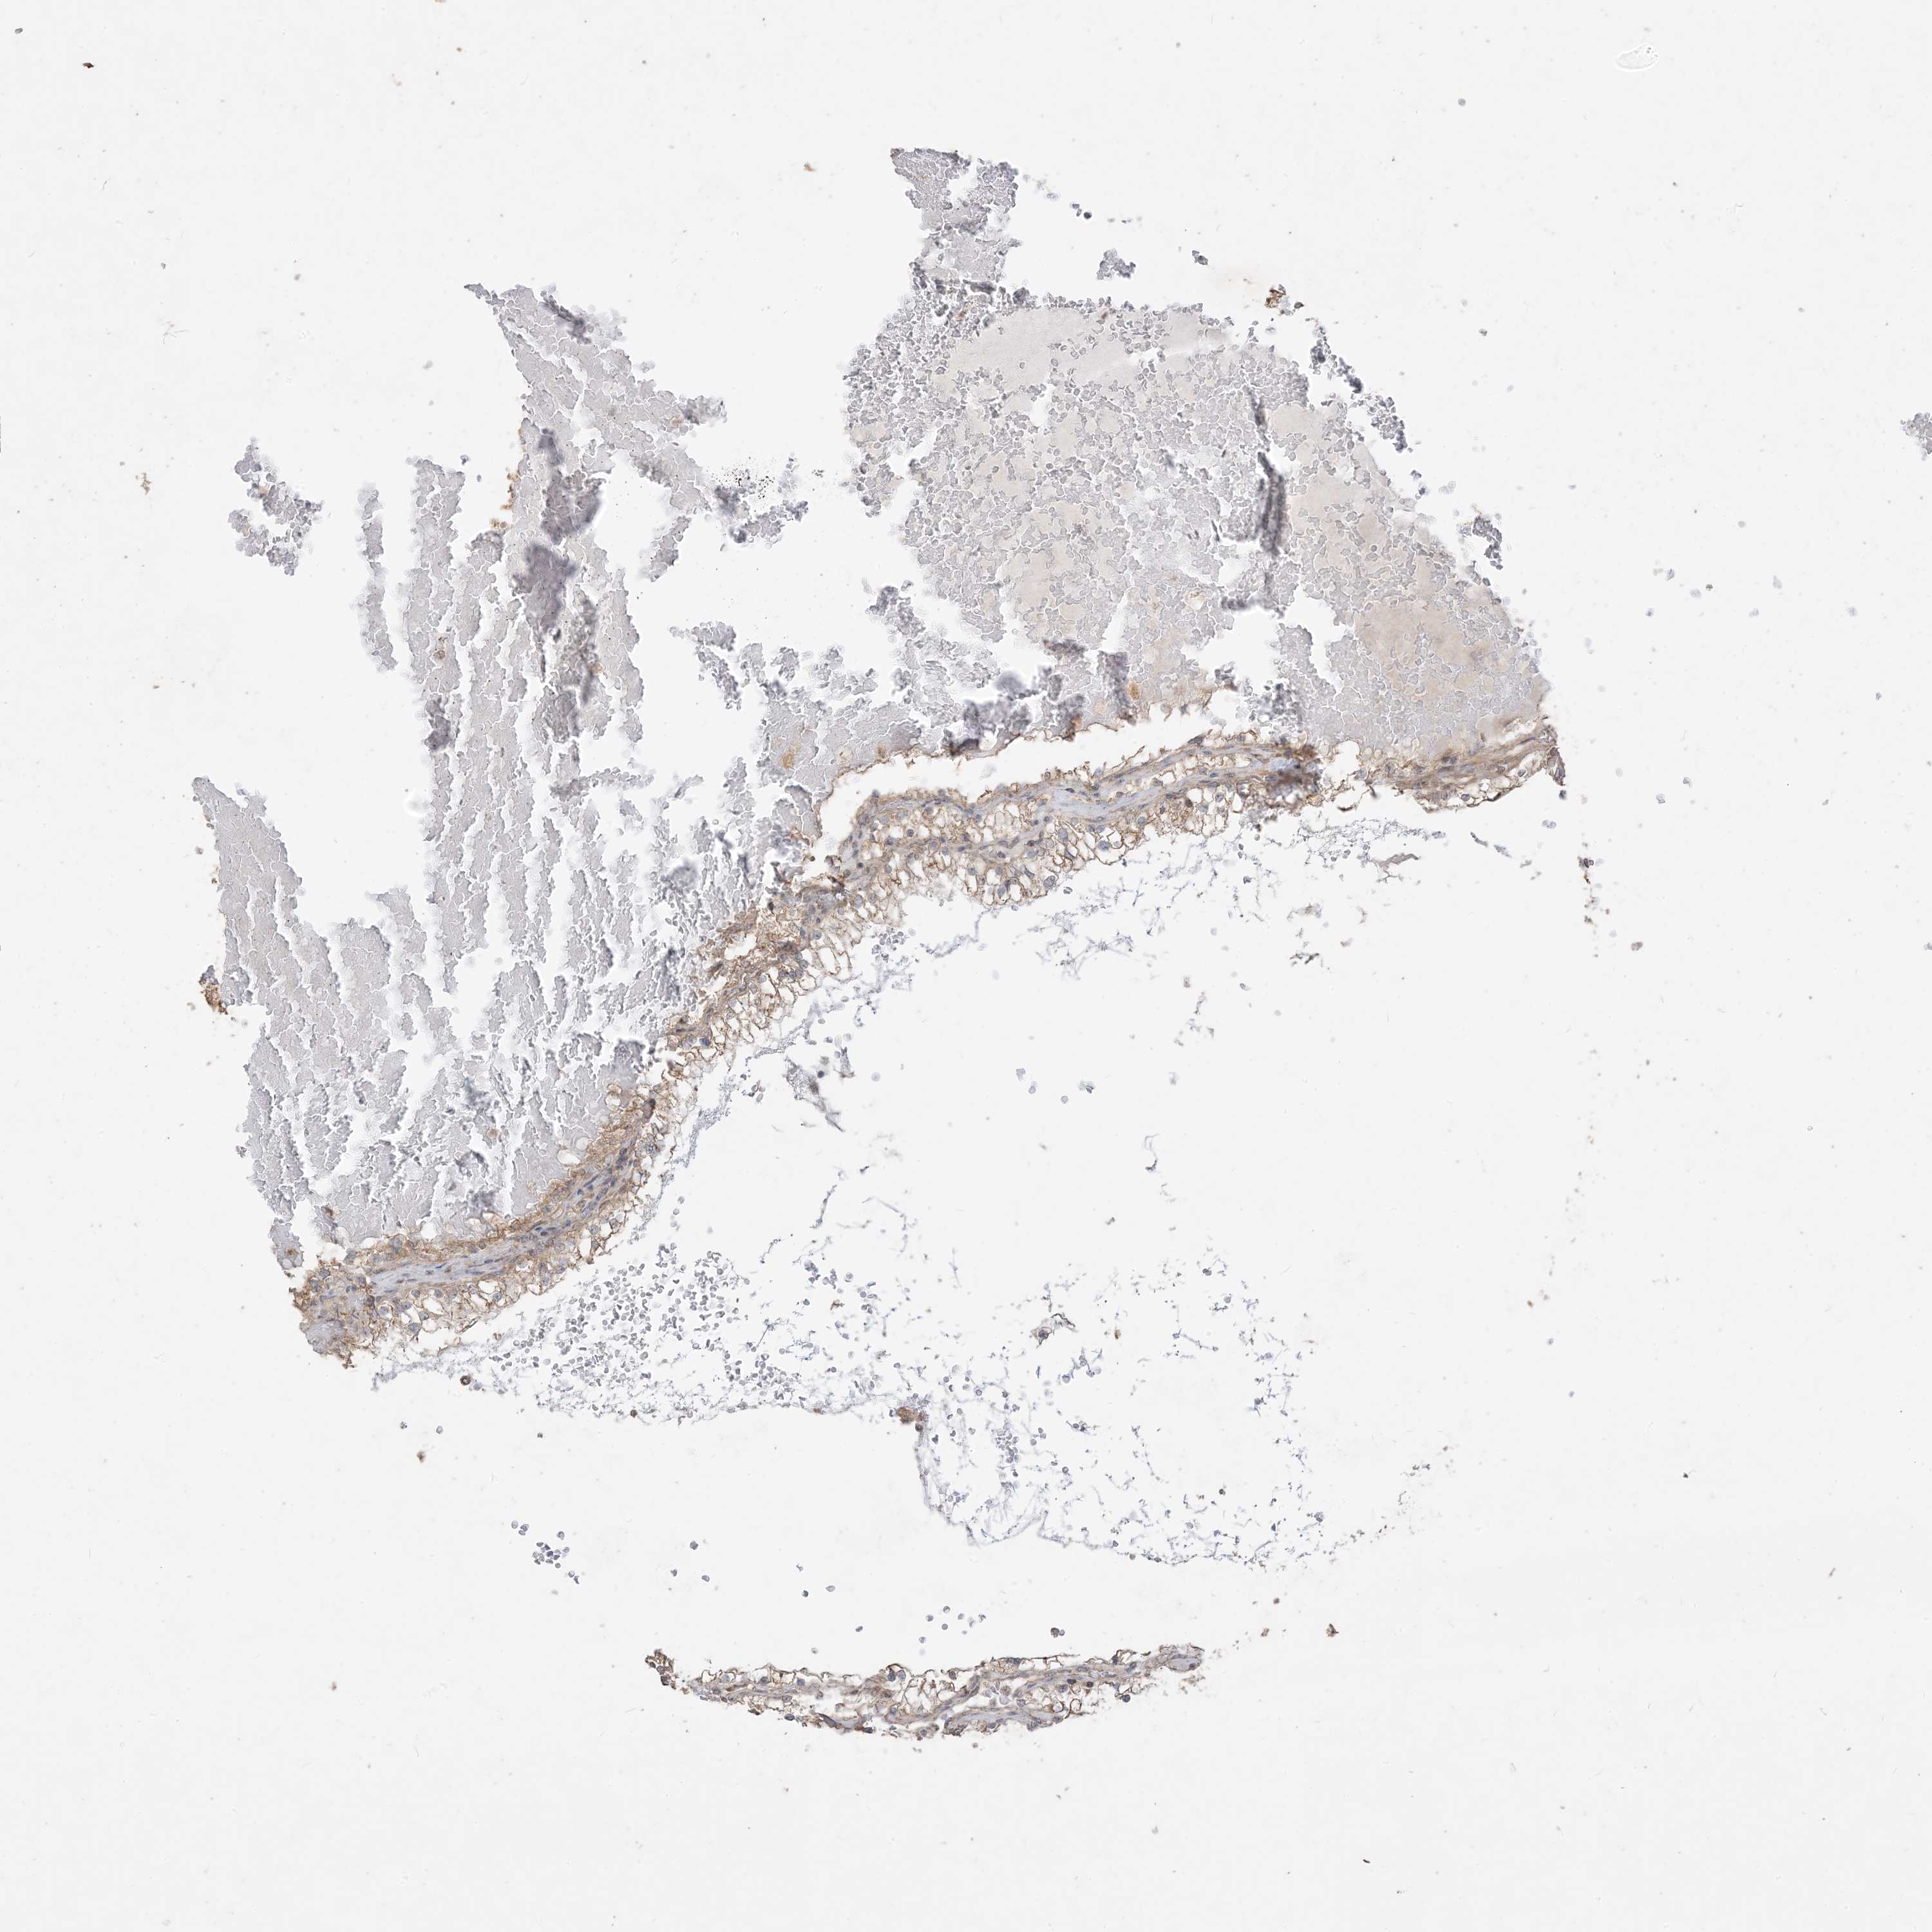

KIDNEY RENAL CLEAR CELL CARCINOMA (VALIDATION) - Interactive survival scatter ploti

The Survival Scatter plot shows the clinical status (i.e. dead or alive) for all individuals in the patient cohort, based on the same data that underlies the corresponding Kaplan-Meier plots. Patients that are alive at last time for follow-up are shown in blue and patients who have died during the study are shown in red.

The x-axis shows the expression levels (FPKM) of the investigated gene in the tumor tissue at the time of diagnosis. The y-axis shows the follow-up time after diagnosis (years). Both axes are complimented with kernel density curves demonstrating the data density over the axes. The top density plot shows the expression levels (FPKM) distribution among dead (red) and alive patients (blue). The right density plot shows the data density of the survived years of dead patients with high and low expression levels respectively, stratified using the cutoff indicated by the vertical dashed line through the Survival Scatter plot. This cutoff is automatically defined based on the FPKM cutoff that minimizes the p-score. The cutoff can be changed by dragging the vertical line or by entering a cutoff value in the square labeled "Current cut-off".

Under the Survival Scatter plot the p-score landscape (black curve; left axis) is shown together with dead median separation (red curve; right axis). Dead median separation is the difference in median mRNA expression between patients who have died with high and low expression, respectively. It is calculated as follows: median FPKM expression of dead patients with high expression - median FPKM expression of dead patients with low expression. This is intended to aid the user in visually exploring custom cutoffs and the associated p-scores and dead median separation.

Individual patient data is displayed and can be filtered by clicking on one or more of the category buttons on the top of the page. Categories describing expression level and patient information include: high, low, alive, dead, female, male and tumor stages. The scale of the x-axis can be toggled between linear and log-scale by clicking on the "x log" button. Mouse-over function shows TCGA ID, patient information and mRNA expression (FPKM) for each patient.

& Survival analysisi

Kaplan-Meier plots summarize results from analysis of correlation between mRNA expression level and patient survival. Patients were divided based on level of expression into one of the two groups "low" (under cut off) or "high" (over cut off). X-axis shows time for survival (years) and y-axis shows the probability of survival, where 1.0 corresponds to 100 percent.

SIRT3 is not prognostic in Kidney Renal Clear Cell Carcinoma (validation)

Best expression cut offi

Based on the FPKM value of each gene, patients were classified into two groups and association between prognosis (survival) and gene expression (FPKM) was examined. The best expression cut-off refers the FPKM value that yields maximal difference with regard to survival between the two groups at the lowest log-rank P-value. Best expression cut-off was selected based on survival analysis .

When clicking on this number, the vertical dashed line indicating cut-off, the interactive survival plot, and the Kaplan-Meier curve will be adjusted to show results based on the best expression cut-off.

: 17.16

P scorei

Log-rank P value for Kaplan-Meier plot showing results from analysis of correlation between mRNA expression level and patient survival.

N/A

5-year survival highi

5-year survival for patients with higher expression than the expression cutoff.

For melanoma and glioma, 3-year survival is shown.

5-year survival lowi

5-year survival for patients with lower expression than the expression cutoff.

TCGA RNA samplesi

RNA-seq data is reported as average FPKM (number Fragments Per Kilobase of exon per Million reads), generated by the The Cancer Genome Atlas (TCGA) .

Normal distribution across the dataset is visualized with box plots, shown as median and 25th and 75th percentiles. Points are displayed as outliers if they are above or below 1.5 times the interquartile range. FPKM values of the individual samples are presented next to the box plot.

Average pTPM 16.1

Number of samples 100